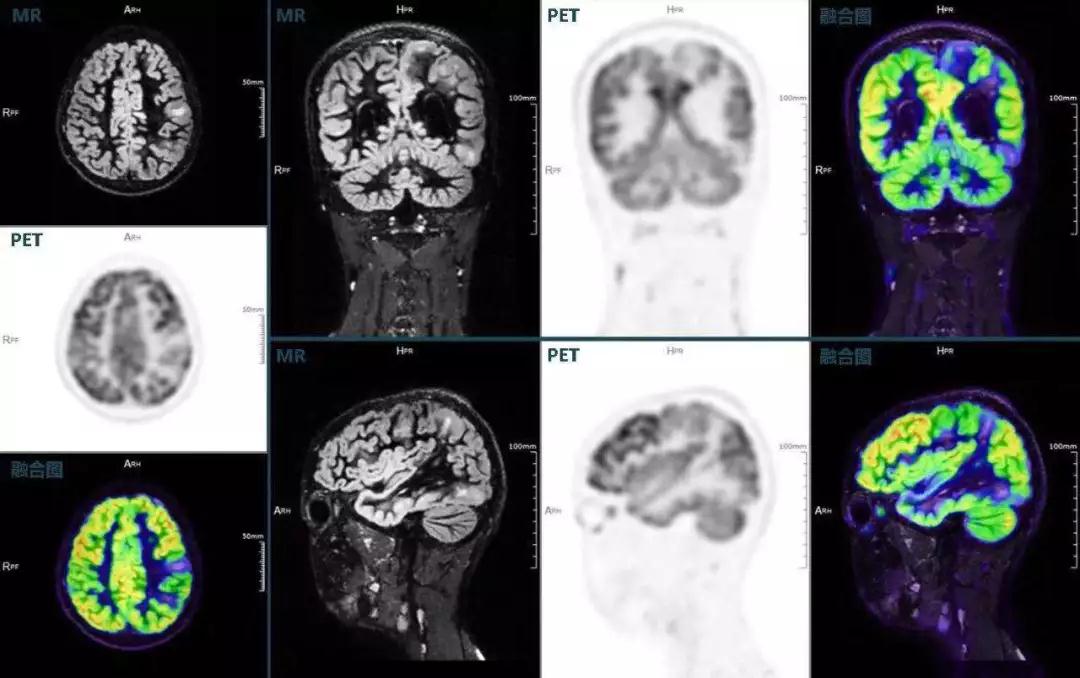

不僅如此,聯(lián)影“時空一體”超清TOF PET/MR還搭載了大量可用于神經(jīng)疾病領(lǐng)域的高級應(yīng)用,如DIR(Double Inversion Recovery雙反轉(zhuǎn)恢復(fù))序列能夠清晰顯示大腦皮層的結(jié)構(gòu)成像,對于皮層腫脹,膠質(zhì)增生等癲癇的影像征象都能清楚呈現(xiàn);DTI(Diffusion Tensor Imaging彌散張量成像)高級應(yīng)用能夠顯示細(xì)小的神經(jīng)纖維束缺損,以更加定量的形式為醫(yī)生提供一個全新的診斷維度,輔助醫(yī)生精準(zhǔn)診斷。

(結(jié)節(jié)性硬化,MR DIR序列清晰顯示腦皮層病理改變,PET顯示了病灶區(qū)域FDG的低濃聚。PET/MR融合顯像同時提供了結(jié)構(gòu)異常改變和功能變化的信息。)